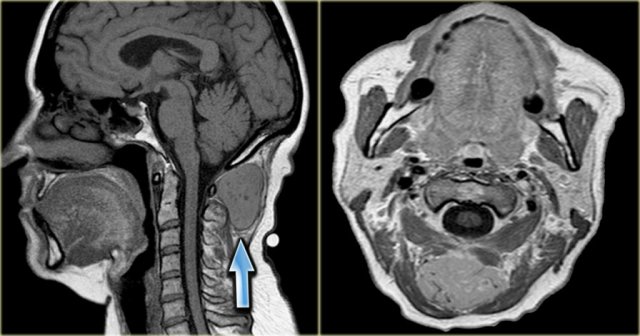

Mechanism of a laryngocele

The laryngeal ventricle (v) is a slit-like opening between the false and true vocal cords (image far left).

It is the anatomic landmark between supraglottis and glottis.

The ventricle extends laterally and then cranially into the paraglottic space.

When the opening of the laryngeal ventricle is completely obstructed by tumor, the mucosa in the paraglottic space continues to produce fluid.

This results in a fluid-filled internal laryngocele.

Eventually the paraglottic space becomes filled up and the internal laryngocele will become external by extending outside of the larynx through the thyro-hyoid membrane.

When the opening of the laryngeal ventricle is partially obstructed, a pressure-valve mechanism may result in an air-containing internal laryngocele which may, eventually, become external (right image, red arrow).